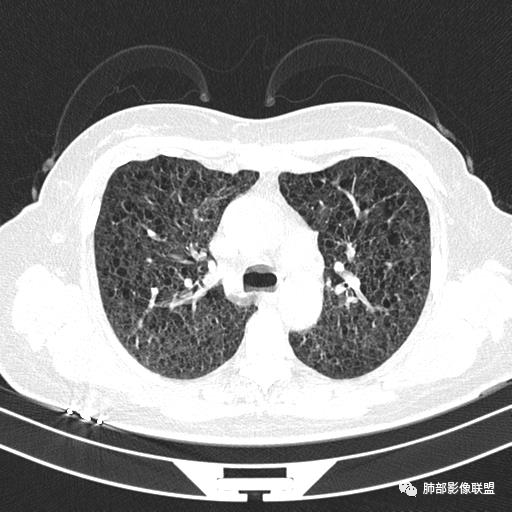

双肺弥漫囊腔,累及肋膈角,囊腔形态相对规则单一。

CT平扫示双肺弥漫分布大小不等囊状薄壁透光区,无内、中、外带分布差异,间质稍示增厚。拟LAM

中年女性育龄期妇女,咳嗽气喘,无吸烟史,有苯吸入史。影像:双肺弥漫均匀小囊腔,无明显分布优势,囊腔形态欠规则,壁薄,部分囊腔边缘血管征,伴双肺弥漫磨玻璃影,无结节,考虑lam,鉴别苯中毒肺损伤,囊腔多有分布优势,小叶中心分布为主,形态规整等

双肺弥漫大小不一薄壁含气囊腔,囊间肺组织正常,正常肺背景,肺尖肺底受累;青年女性,气喘,支持LAM

CT表现:双肺弥漫大小不等的薄壁囊腔,囊壁<2mm,外形规则,血管影多位于囊腔周围,囊腔之间肺组织正常,随着疾病进展到晚期,囊腔变大、增多,不可胜数,囊腔可融合成较大的囊,与肺气肿相似,形成间质性肺纤维化。部分病例可出现结节影。